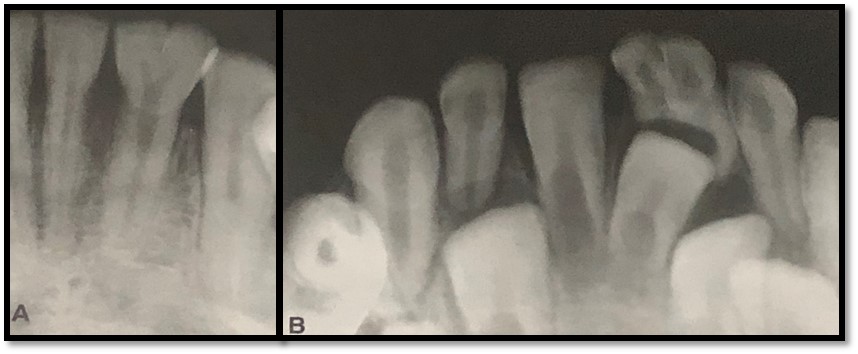

As radiografias são exames essenciais no diagnóstico destas anomalias de desenvolvimento dental (forma) pois permitem observar melhor a extensão da união e a presença dos condutos radiculares e raízes e orientar o tratamento.

Assim, permitem a segurança ao orientar o profissional quanto ao tratamento específico do dente, juntamente com o exame clínico. Trago pra vocês um caso não tão comum de fusão de molares (Figura 3, A e B). Observem atentamente a imagem. Neste caso o diagnóstico diferencial da fusão incluem: geminação e macrodontia.